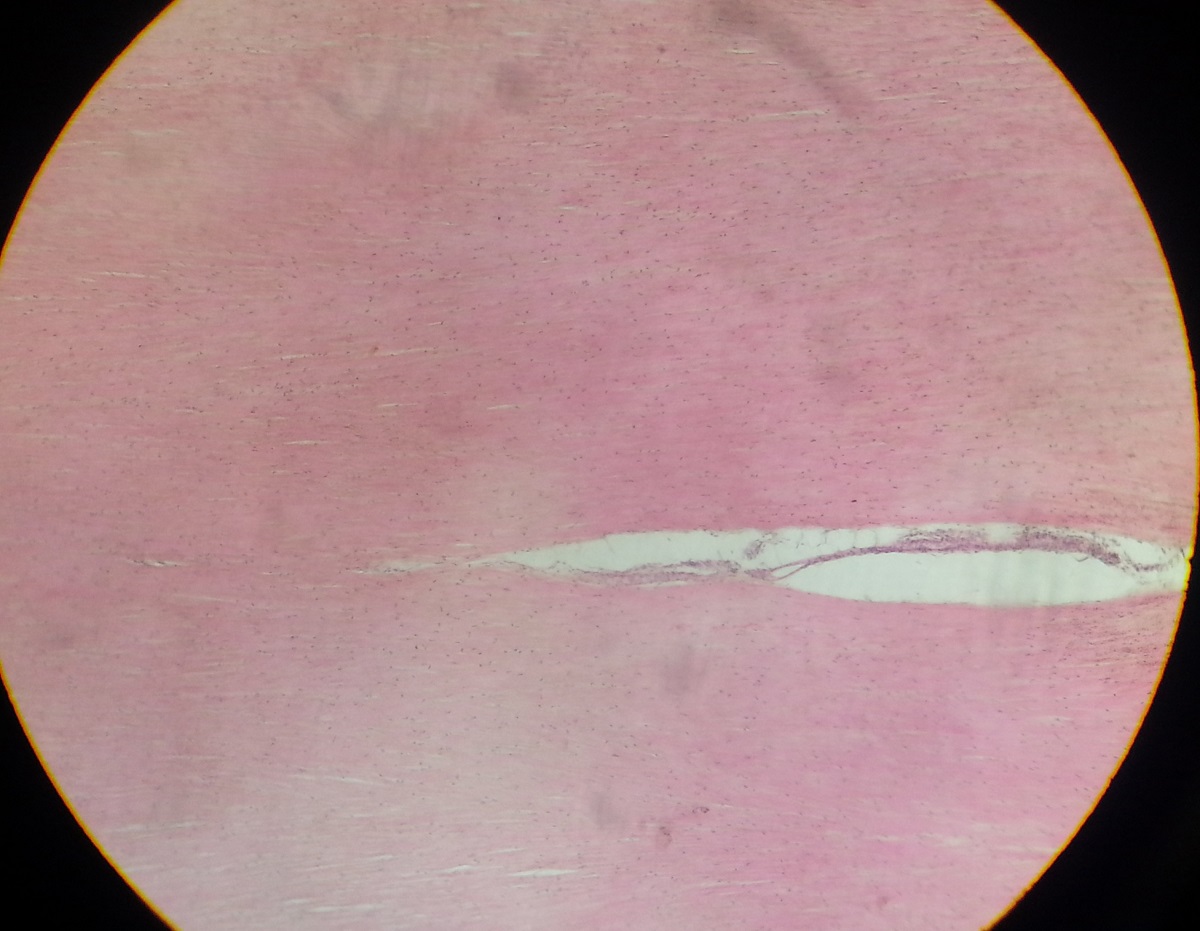

Tendon

Compact linear collagen fibers seen.

Few scattered, inactive fibroblasts with nuclei

Poor vascularity, tiny nerve endings and tendon stretch receptors see.